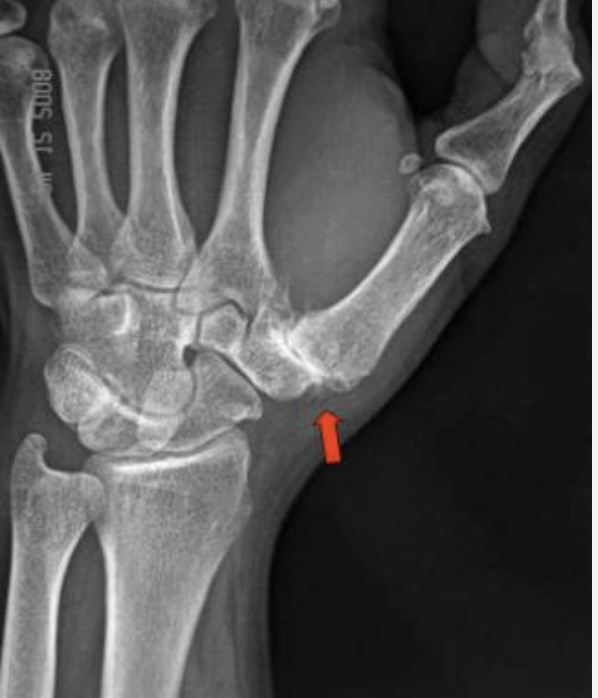

CMC arthritis presents along a spectrum from ligamentous laxity in young patients to end-stage bone-on-bone arthritis in older patients. The Eaton-Littler radiographic staging system guides treatment:

Stage I | Normal joint space. Synovitis and ligamentous laxity only. Treated conservatively. |

Stage II | Joint space narrowing <1/3. Small osteophytes. Subchondral sclerosis. Conservative treatment; injection highly effective. |

Stage III | Joint space narrowing >1/3. Large osteophytes. Adduction of the first metacarpal. Conservative treatment failing; surgical intervention likely. |

Stage IV | Complete joint destruction, involving STT joint. Surgical treatment required. |